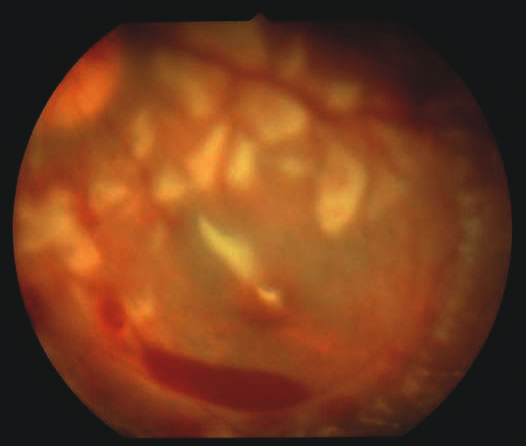

Findings range from a normal fundus to a small number of scattered intraretinal hemorrhages in the posterior pole to massive, confluent hemorrhages from the posterior pole to the ora serrata.(Fig. 10) The hemorrhages may be subretinal, deep intraretinal (dot/blot), nerve fiber layer (flame shaped) or preretinal.19,45 Intraretinal hemorrhages are more common than preretinal or subretinal hemorrhages.32,46 Preretinal hemorrhages must be distinguished from traumatic retinoschisis (see later), which has particular diagnostic significance. White-centered retinal hemorrhages, although classically associated with endocarditis, can occur in any condition that causes retinal hemorrhages, including SBS. Vitreous hemorrhage may be small to massive, and may occur secondary to escape of blood from intraretinal collections or from torn vessels.19 Although vitreous hemorrhage may occur at the time of injury, it may also be a delayed finding occurring 1 to 3 days or more after the initial trauma.47,48

The pathophysiologic mechanisms of retinal hemorrhage in SBS are varied. Vitreous and perhaps orbital shaking is likely to be involved in most of the vitreoretinal injuries. In children, the vitreous is well attached to the retina at the macula, blood vessels, and the periphery. Shaking of an infant causes the vitreous to shake, which, in turn, applies shearing forces to the retina at points of firm attachment. These shearing forces at the macula may split the retina at any layer, causing the formation of a cystic cavity, which may be filled partially or completely with blood (Fig. 11). This traumatic retinoschisis has been well documented in abuse cases by ultrasound, electroretinogram, and pathology.34,58,60,61,62,63,64 Histopathology reveals a widening of the retinal layers or a stripping of the internal limiting membrane. The vitreous may stay adherent or detach. Clinically, to recognize this important finding in SBS, the examiner may observe a hemorrhagic or hypopigmented curvilinear edge to the schisis cavity, with or without a fold in the retina (Figure 11).50,65,66 Recognition of this edge helps distinguish retinoschisis from subhyaloid hemorrhage. However, subhyaloid hemorrhage, which may have originated from blood breaking out of a schisis cavity, may obscure the underlying schisis. It is important to follow any potentially shaken child with preretinal blood in the macula until that blood has cleared as the signs of schisis may be unmasked as the blood resorbs thus confirming the diagnosis of SBS. The retinal fold or hypopigmented line may be a complete circle or just an arc. In the long term, these patients may have surprisingly few sequelae and good vision as the cavity flattens spontaneously. There may also be findings of permanent curvilinear, hypopigmented scars or retinal folds. These provide clues to prior abuse.67

There remain still other theories for retinal hemorrhage in SBS that also seem to play a minor role. Some have suggested a Purtscher-like mechanism due to an increase in intrathoracic pressure when the perpetrator squeezes the child's chest. Although the characteristic white retinal patches of Purtscher retinopathy may be seen in SBS (Fig. 11), there appears to be no correlation with rib fractures,35 and the finding is very uncommon. The failure to see significant retinal hemorrhaging after the chest compressions of cardiopulmonary resuscitation in both animal models and humans also argues against a Purtscher-like mechanism.

The differential diagnosis of retinal hemorrhages in a child is vast. However, if one considers a child with the full spectrum of injuries seen in SBS, including brain, skeletal, and eye findings, most would not dispute that the retinal findings are due to nonaccidental injury. However, in a child with a small number of retinal hemorrhages and without retinoschisis, (Fig. 10A) the diagnosis of SBS may be less clear.